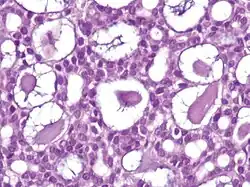

Nodular basal-cell carcinoma

.jpg)

Nodular basal-cell carcinoma (also known as "classic basal-cell carcinoma") accounts for 50% of all BCC.[29] It most commonly occurs on the sun-exposed areas of the head and neck.[30]: 748 [31]: 646 Histopathology shows aggregates of basaloid cells with well-defined borders, showing a peripheral palisading of cells and one or more typical clefts.[29] Such clefts are caused by shrinkage of mucin during tissue fixation and staining.[32] Central necrosis with eosinophilic, granular features may also be present, as well as mucin. The heavy aggregates of mucin determine a cystic structure. Calcification may also be present, especially in long-standing lesions.[29] Mitotic activity is usually not so evident, but a high mitotic rate may be present in more aggressive lesions.[29] Adenoidal BCC can be classified as a variant of NBCC, characterized by basaloid cells with a reticulated configuration extending into the dermis.[29]

Cleft.